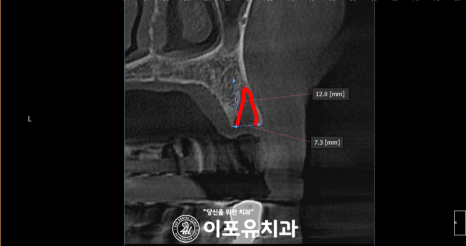

엑스레이 사진을 보면

위턱 측절치에 우식증이 보이고

작은 어금니부터 대구치까지

이어진 염증이 눈에 띄는데요.

이것 때문에 통증을 느꼈을 것입니다.

더 정확하게 진료하기 위해